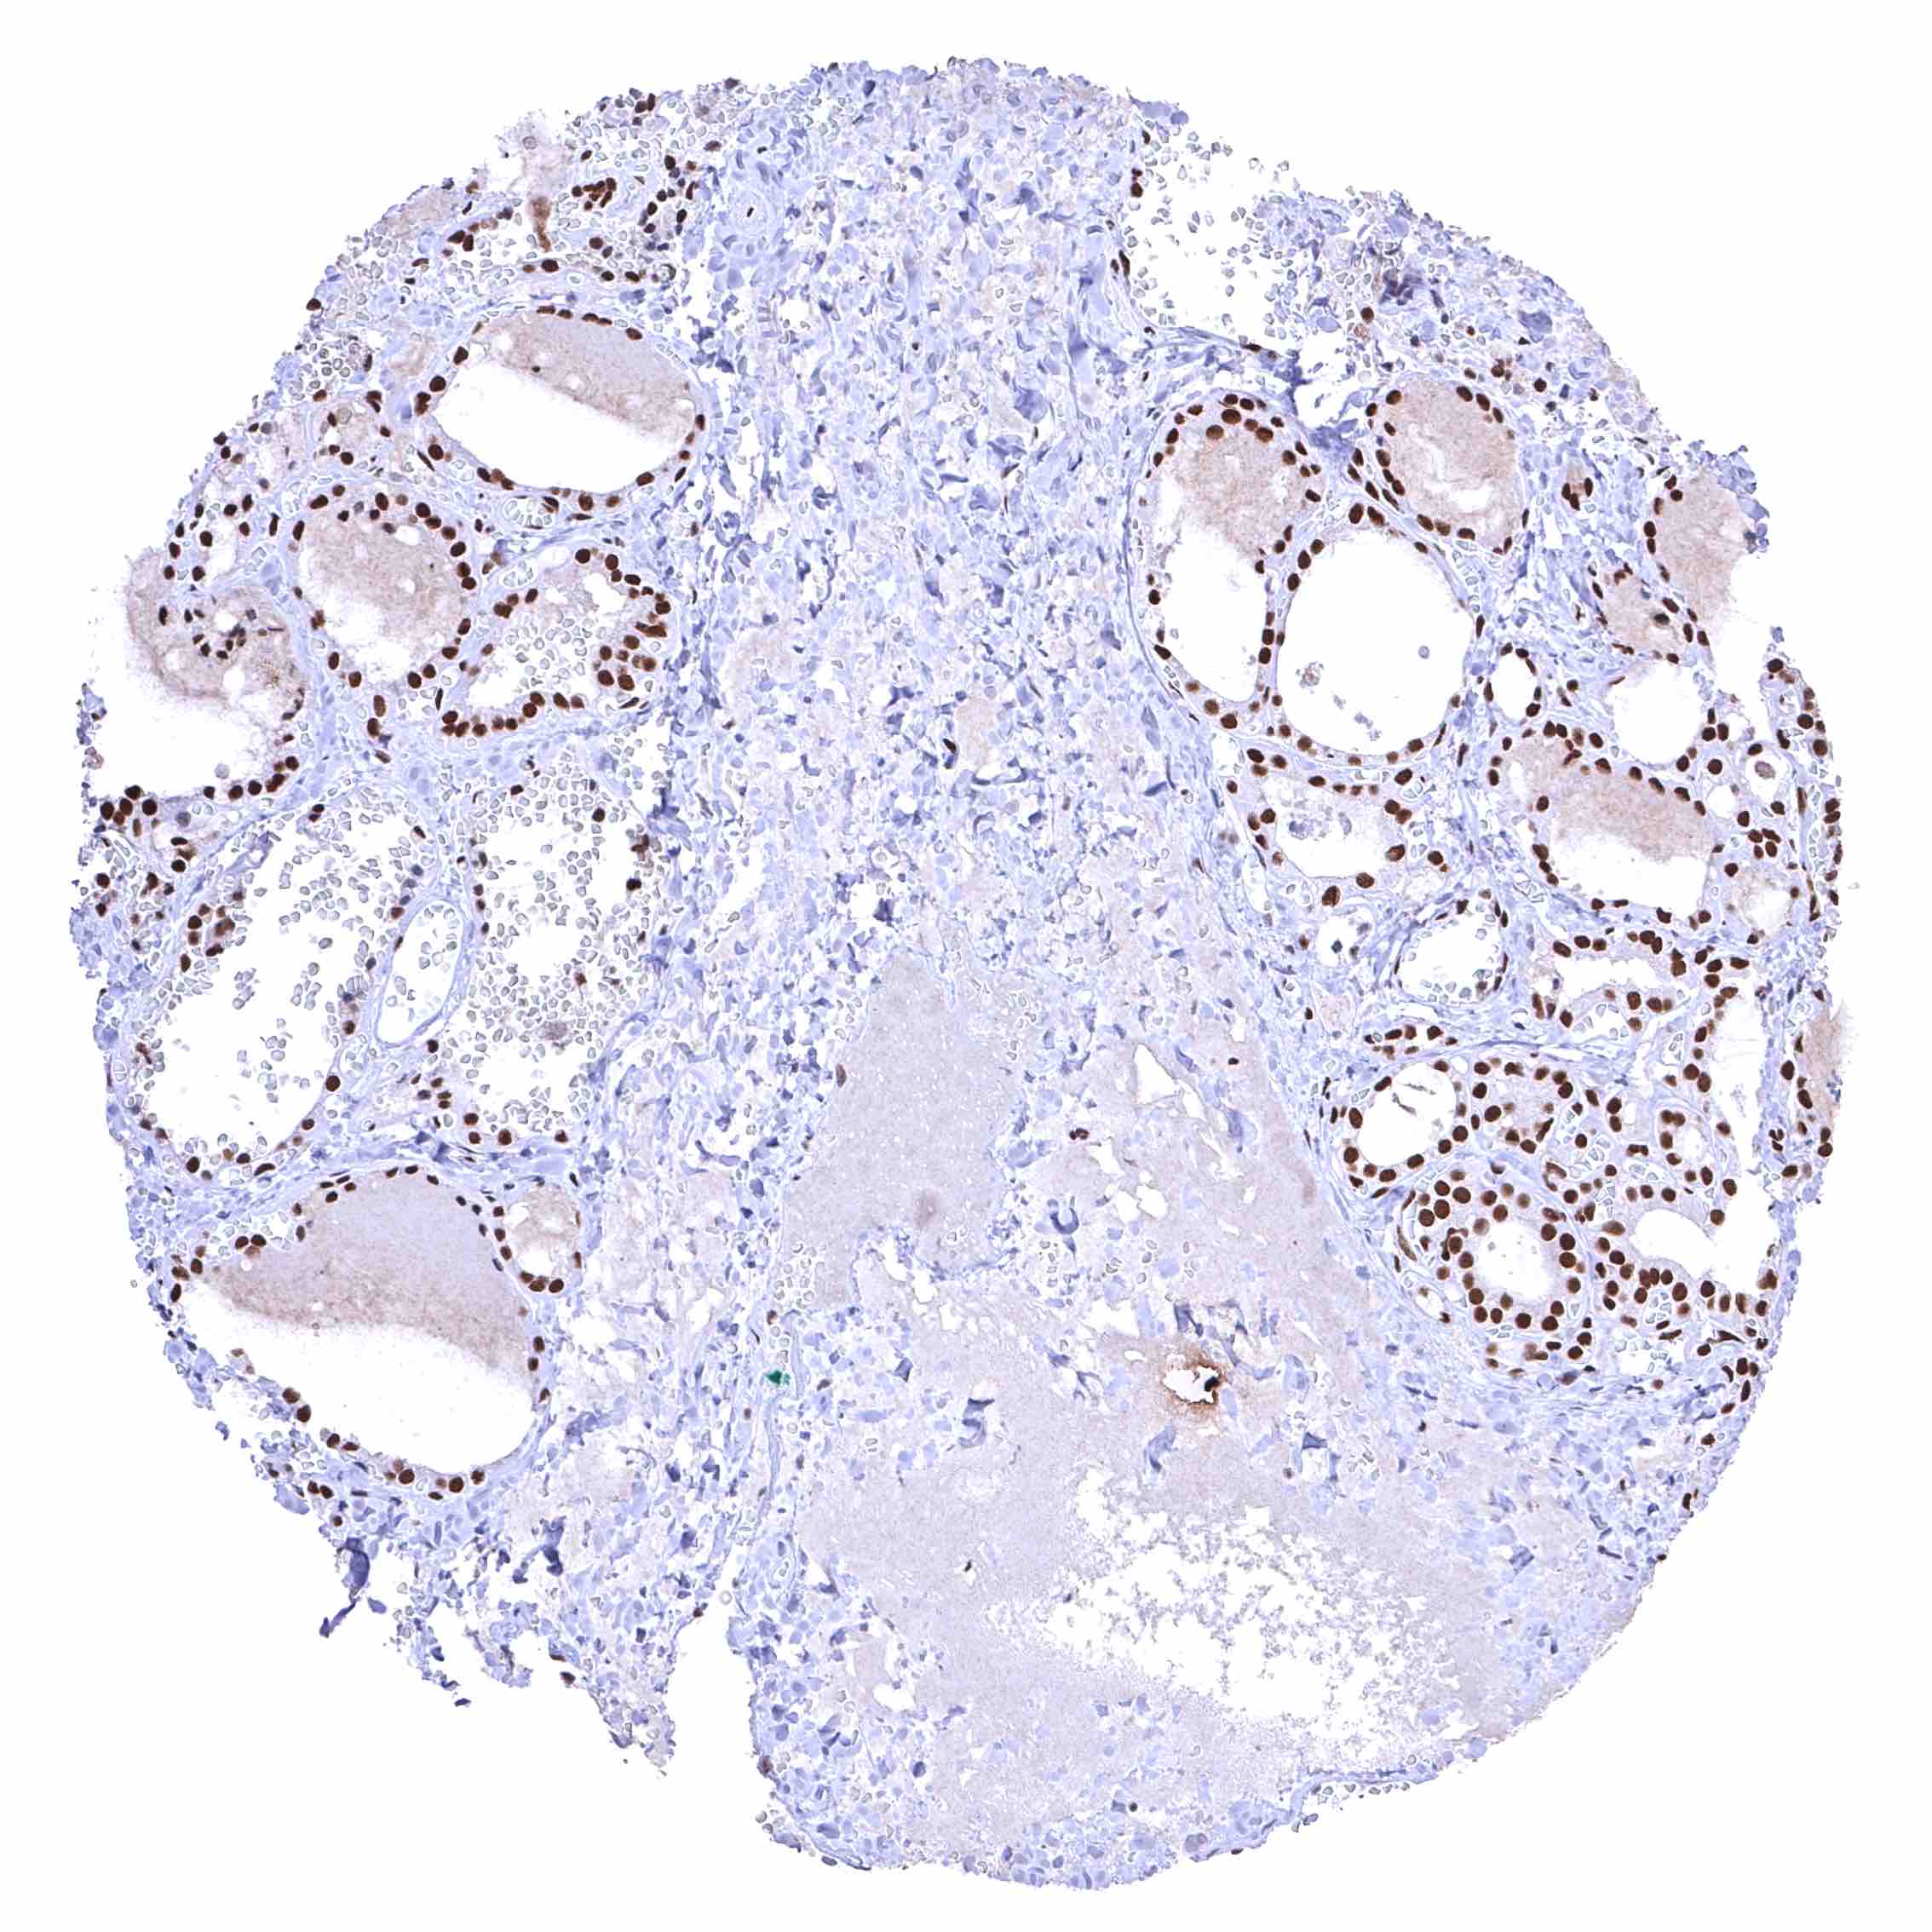

BRD4 antibody [HMV4275] HistoMAX™

Testis – The level of nuclear BRD4 staining decreases with maturation of germ cells.